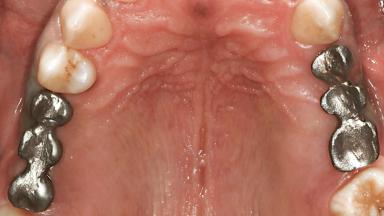

In the summer of 2002, a 42-year-old female patient was referred to the University of Geneva for the replacement of posterior maxillary and mandibular missing or non-restorable teeth.The patient’s medical history revealed no significant findings,and she was in good general health.Her dental history included recurrent decay that led to the loss of several posterior teeth. The patient showed no history of periodontal disease. At the extraoral examination, the patient presented normal physiognomy with normal facial and lip support and homogenous distribution of the facial thirds. At full smiling, the patient displayed an average lip line, and a tooth gap was slightly visible in the left maxilla. Small diastemas were present between the anterior maxillary teeth.